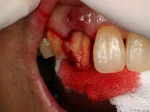

前歯即時埋入症例

術前術前主訴-前歯が腫れて痛い。治療法のうち、ブリッジとインプラントを説明して隣の前歯を削らないですむことからインプラントを選択された。 術前レントゲン術前レントゲン術前レントゲン 抜歯抜歯抜歯を行う。折れていた位置がかなり深い位置であるのがわかる。 歯根も抜歯歯根も抜歯

歯根も抜歯歯根も抜歯歯根も抜歯 抜歯した穴をよく掃除抜歯した穴をよく掃除抜歯した穴をよく掃除(掻爬)後すぐにインプラントを埋入 埋入直後のレントゲン埋入直後のレントゲン埋入直後のレントゲン。上部に見えるのは抜いた歯を利用して両どなりの歯に接着して一時的に使えるようにした。 二次オペ時二次オペ時